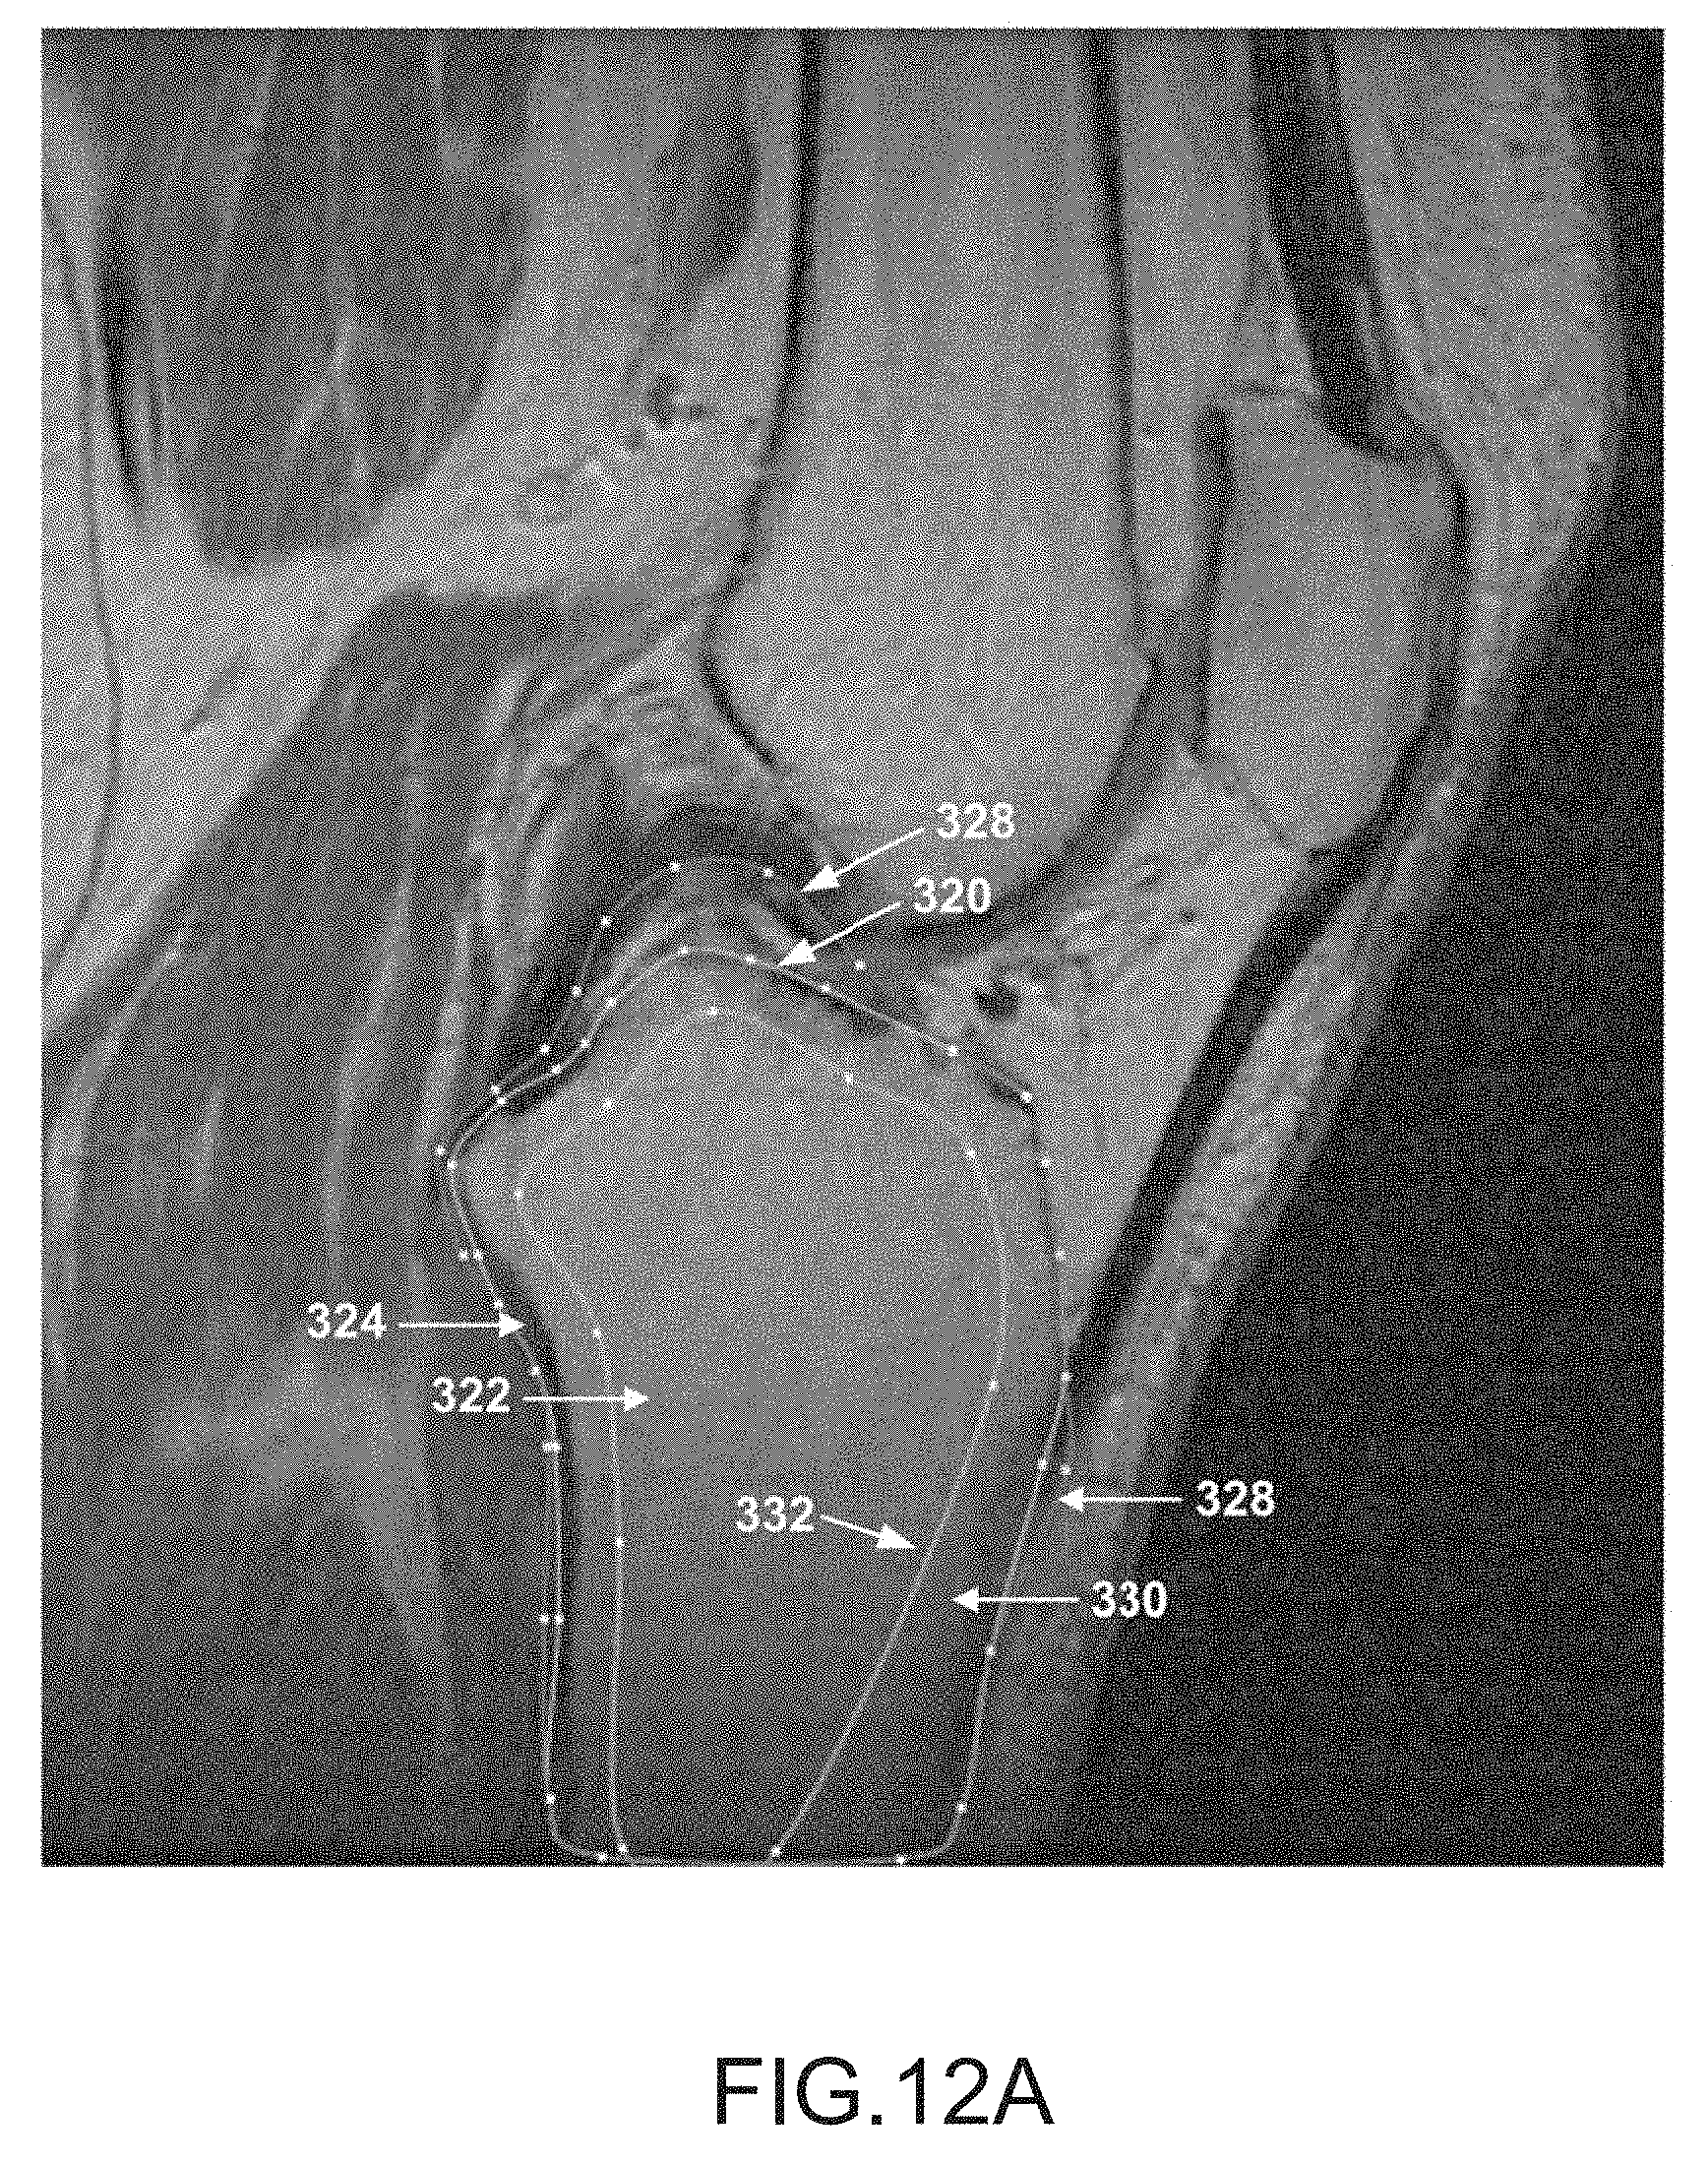

FIG. 12A is a sagittal plane image slice depicting a contour curve outlining a golden tibia region, a contour curve outlining a grown tibia region and a contour curve outlining a boundary golden tibia region.

[0066]